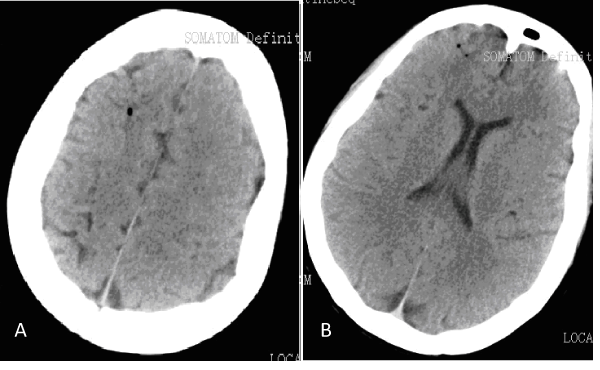

Five days later, the internal jugular venous catheter was planned to remove. She was instructed in supine position and holding breath when the internal jugular vein catheter was pulled out. The exit site was pressed with gauze for 1 minute, and then fixed by the tapes. She was asked to keep in supine. She was suddenly onset of shortness of breathing, consciousness loss and convulsion after 3 minutes. Given 100% oxygen by non-rebreathing mask ventilation, then the endotracheal intubation was implementing. Her blood pressure was 158/108mmHg; pulse rates were 119 beats per minute with regular and sinus rhythm. Pupils were of normal size and reacting symmetrically. Emergency head CT scans showed the signs of cerebral air embolism on the right frontal lobes of the brain (Figure 1). She was diagnosed as paradoxical cerebral air embolism and transferred to ICU. She regained consciousness after 3 hours and the endotracheal tube was removed. She presented hoarseness and paralysis on the left extremities with grade zero power. The right lower extremity was grade four powers. She was received the hyperbaric oxygen therapy twice a day for the first week. She was shifted to a stroke rehabilitation facility and continued hyperbaric oxygen therapy once a day. After two weeks rehabilitation, the left and the right lower extremities were grade four powers, her left upper extremity remained with grade zero power. Four weeks later, her hoarseness disappeared. Both of her lower extremities were grade five powers. She could walk independently after five weeks. Her left upper extremity was grade four powers. We searched in PubMed, EMBASE and Google Scholar for relevant articles from Jan 2000 to Jun 2013. Key word included cerebral air embolism, paradoxical cerebral air embolism, retrograde cerebral air embolism, central venous catheter removal. Five similar case reports were found (Table 1).

Figure 1 Head CT images reveal air bubble in right frontal lobe.